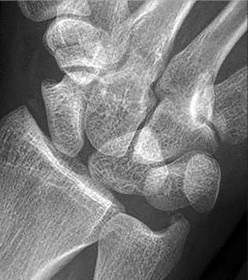

A 22-year-old male sustains a proximal pole scaphoid fracture. Which of the following best describes the predominant arterial supply to the scaphoid that makes this specific fracture pattern highly prone to avascular necrosis (AVN) and nonunion?

The scaphoid is primarily supplied by the dorsal carpal branch of the radial artery (supplying 70-80% of the bone, including the proximal pole). These vessels enter the scaphoid distally at the dorsal ridge and flow in a retrograde fashion toward the proximal pole. Because of this retrograde blood supply, fractures at the proximal pole disrupt the vascularity to the proximal fragment, leading to high rates of AVN and nonunion.